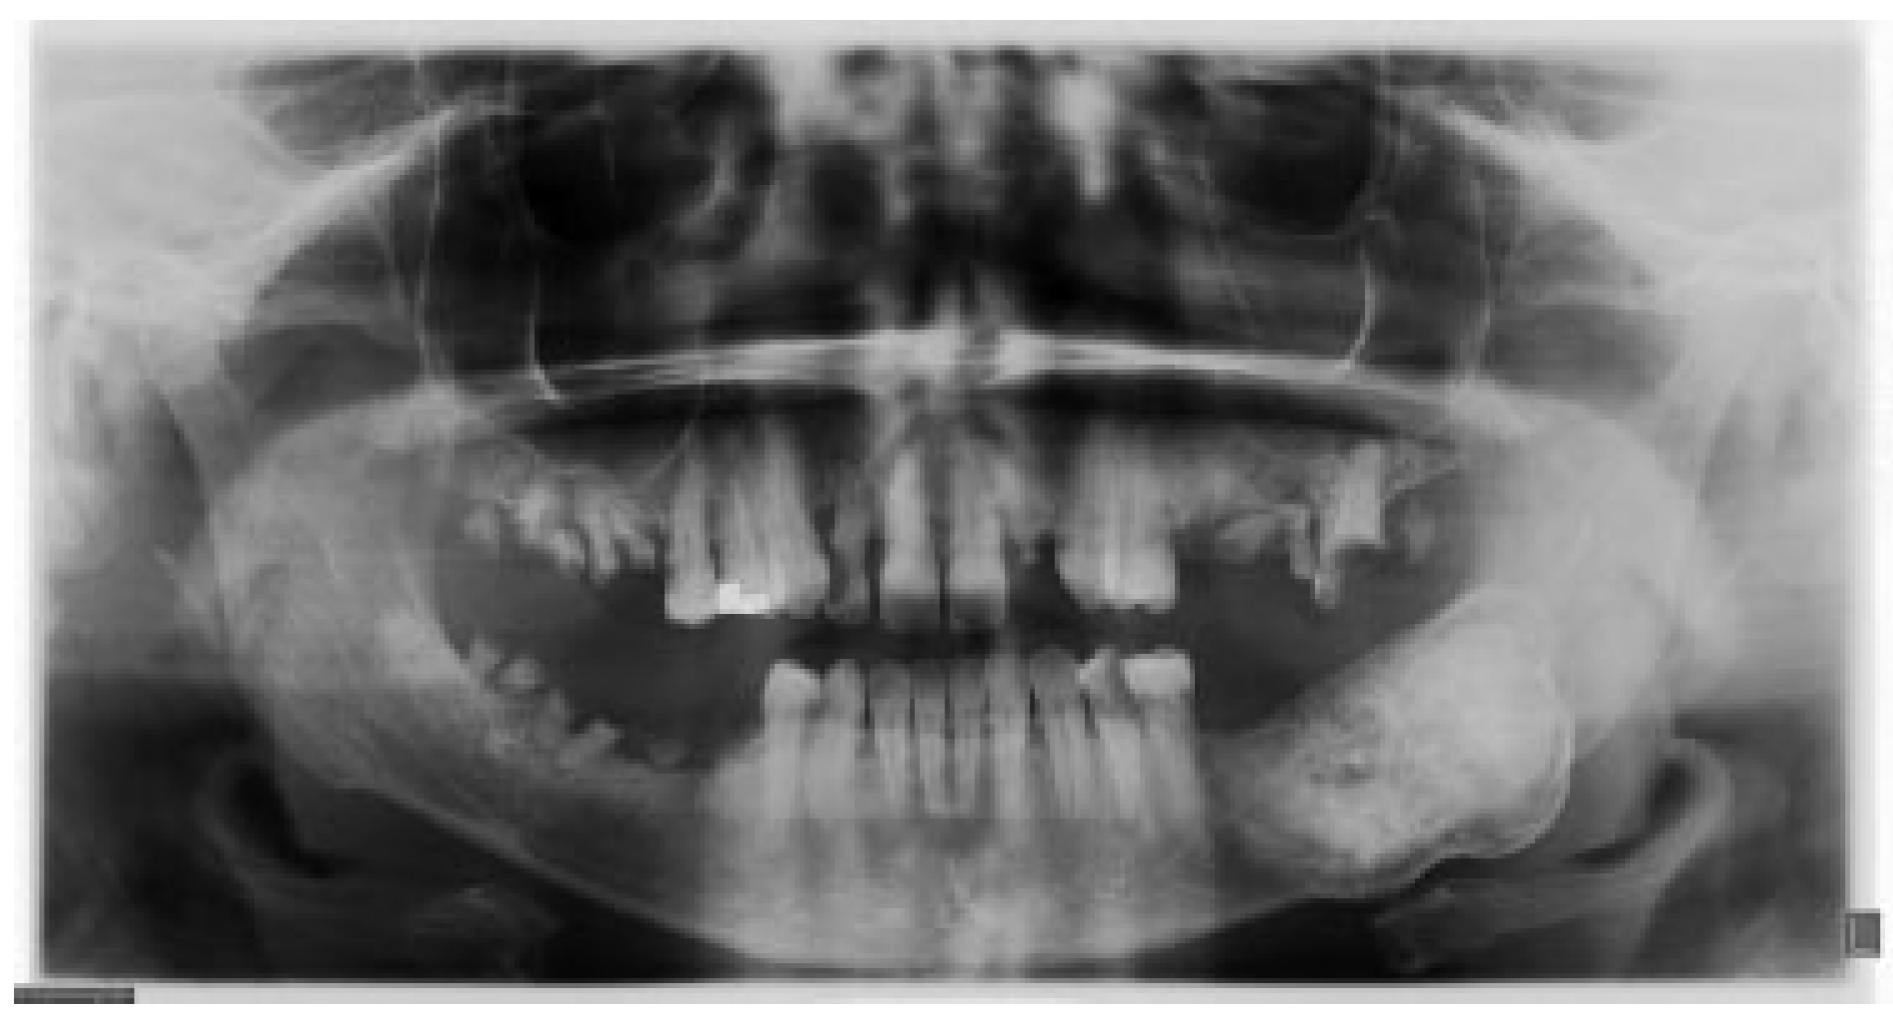

A 46-year-old Caucasian female presented to the Oral Surgery Department at Alameda County Medical Center–Highland General Hospital, complaining of dental pain in maxillary left region for 2 months. Her medical history was significant for hypertension and congestive heart insufficiency for which she takes enalapril, carvedilol, furosemide, and Klor-Con (Klor- Con®, Upsher-Smith Laboratories, Inc., Morristown, NJ) (potassium chloride). She is allergic to codeine. She has a 10 pack- year history of smoking and a remote history of methamphetamine use. Her past surgical history is significant for parathyroid carcinoma, which resulted in primary HTP. She reported that time weight loss, hives, insomnia, fatigue, and bone pain before surgical excision performed 17 years ago. No uterine or kidney lesions were present. She also reported that her brother had a jaw tumor, not surgically treated, because the “jaw growth stopped.” Unfortunately, her brother does not live in the city, and a better investigation concerning his disease could not be performed. Extraoral examination revealed a small swelling in the left mandibular border. Intraorally, the patient presented with poor hygiene with multiple extensive dental caries and periodontal disease. An asymptomatic and firm posterior left mandibular swelling was also present, with buccal and lingual expansion. Radiographic and computed tomography (CT) scan examination revealed a 5-cm mixed radiolucent and radiopaque image in the left mandibular body with well-defined borders and base expansion (Figure 1 and Figure 2a,b). An incisional biopsy was obtained with an intraoral approach which was diagnosed as a benign fibro-osseous lesion, consistent with ossifying fibroma. Initial laboratory analysis prior surgery showed a small increase in serum calcium of 10.5 mg/dL (8.4–10.2 mg/dL). Based on these findings and with the history of parathyroid carcinoma, the patient was referred to an endocrinologist. CT scan of the neck was unequivocal for recurrence and no correction of serum calcium was necessary. The association of ossifying fibroma with primary HPT due parathyroid carcinoma, with a family history of a similar jaw lesion, led to a high suspicion of HPT-JT syndrome. It was extensively discussed with the patient, but she refused to perform any genetic test. Our treatment planning initially included the extraction of the left inferior premolars, which had extensive caries lesions and mobility, performed before the lesion surgical removal. It would enable a better wound closure after resection. Three months later (2010 March), the ossifying fibroma was surgically resected with 5 mm margins (Figure 3) using an intraoral approach, and a 2.4-mm reconstruction plate was placed from the left mandibular ramus to the parasymphysis (Figure 4a–c). The postoperative course was remarkable only for neurosensory disturbance in the left inferior alveolar nerve, which improved but was not completely resolved after 3 years of follow-up. Seven months later (2010 October), using an extraoral approach, the patient underwent a left mandibular reconstruction using her left posterior iliac crest, as well as the right anterior iliac crest. The corticocancellous blocks were secured with 2.4 mm monocortical screws, while cancellous bone chips were inserted between the block grafts (Figure 5a–c). Although regular follow-ups were performed within the first 4 postoperative months, the patient recently returned to the oral surgery clinic for revaluation in 2012. Clinical and radiological examinations (Figure 6) were performed, and oral rehabilitation with dental implants was planned (June 2012). The patient subsequently underwent a third surgical intervention, under local anesthetic and intravenous sedation. The remaining maxillary teeth were extracted, followed by osteoplasty and placement of four implants: two anterior axially placed and two posterior tilted placed. At the same operating time, monocortical screws were from the mandible and three implants were placed in the region of teeth 20, 21, and 28, and alloplastic bone graft was placed covering the exposed threads of the implants (Figure 7a,b). A temporary superior and inferior prostheses were subsequently placed, and a period of 6 months for implant osseointegration before final prosthesis rehabilitation is being observed. The patient is currently followed regularly and, after 3 years of surgical resection, no evidenceof tumor recurrence is seen (Figure 8). Therefore, no evidence of parathyroid carcinoma recurrence is seen after 21 years of endocrinological follow-up.

Figure 1. Radiographic examination showing the lesion in the left body mandible.